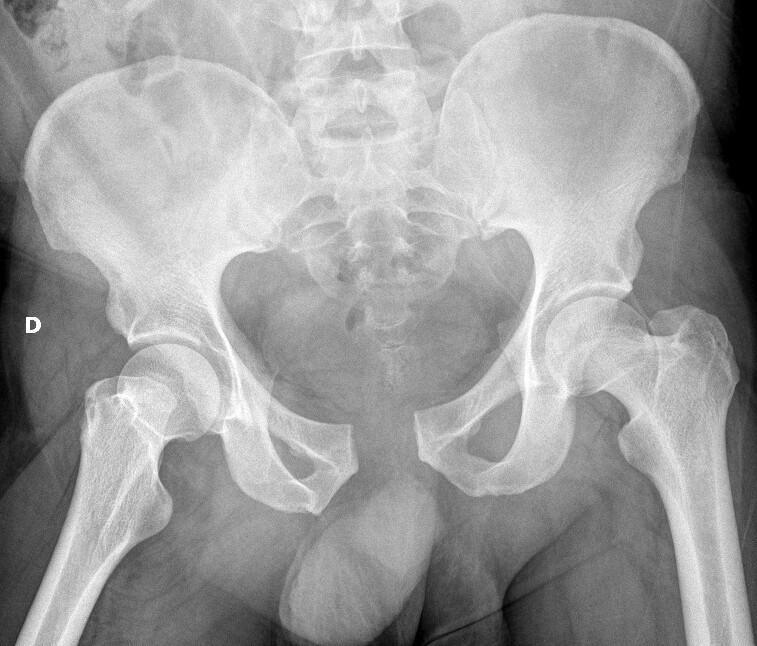

Leonardo Lustosa, Radiopaedia.org. From the case rID: 99312

Fracture type A parcellaire

Exemple : Fracture de l’épine iliaque

- Antéro-supérieure

- Antéro-inférieure

- Fracture de l’aile iliaque

- Fracture de l’ischion (grand écart, souvent adolescent, gym, foot…)